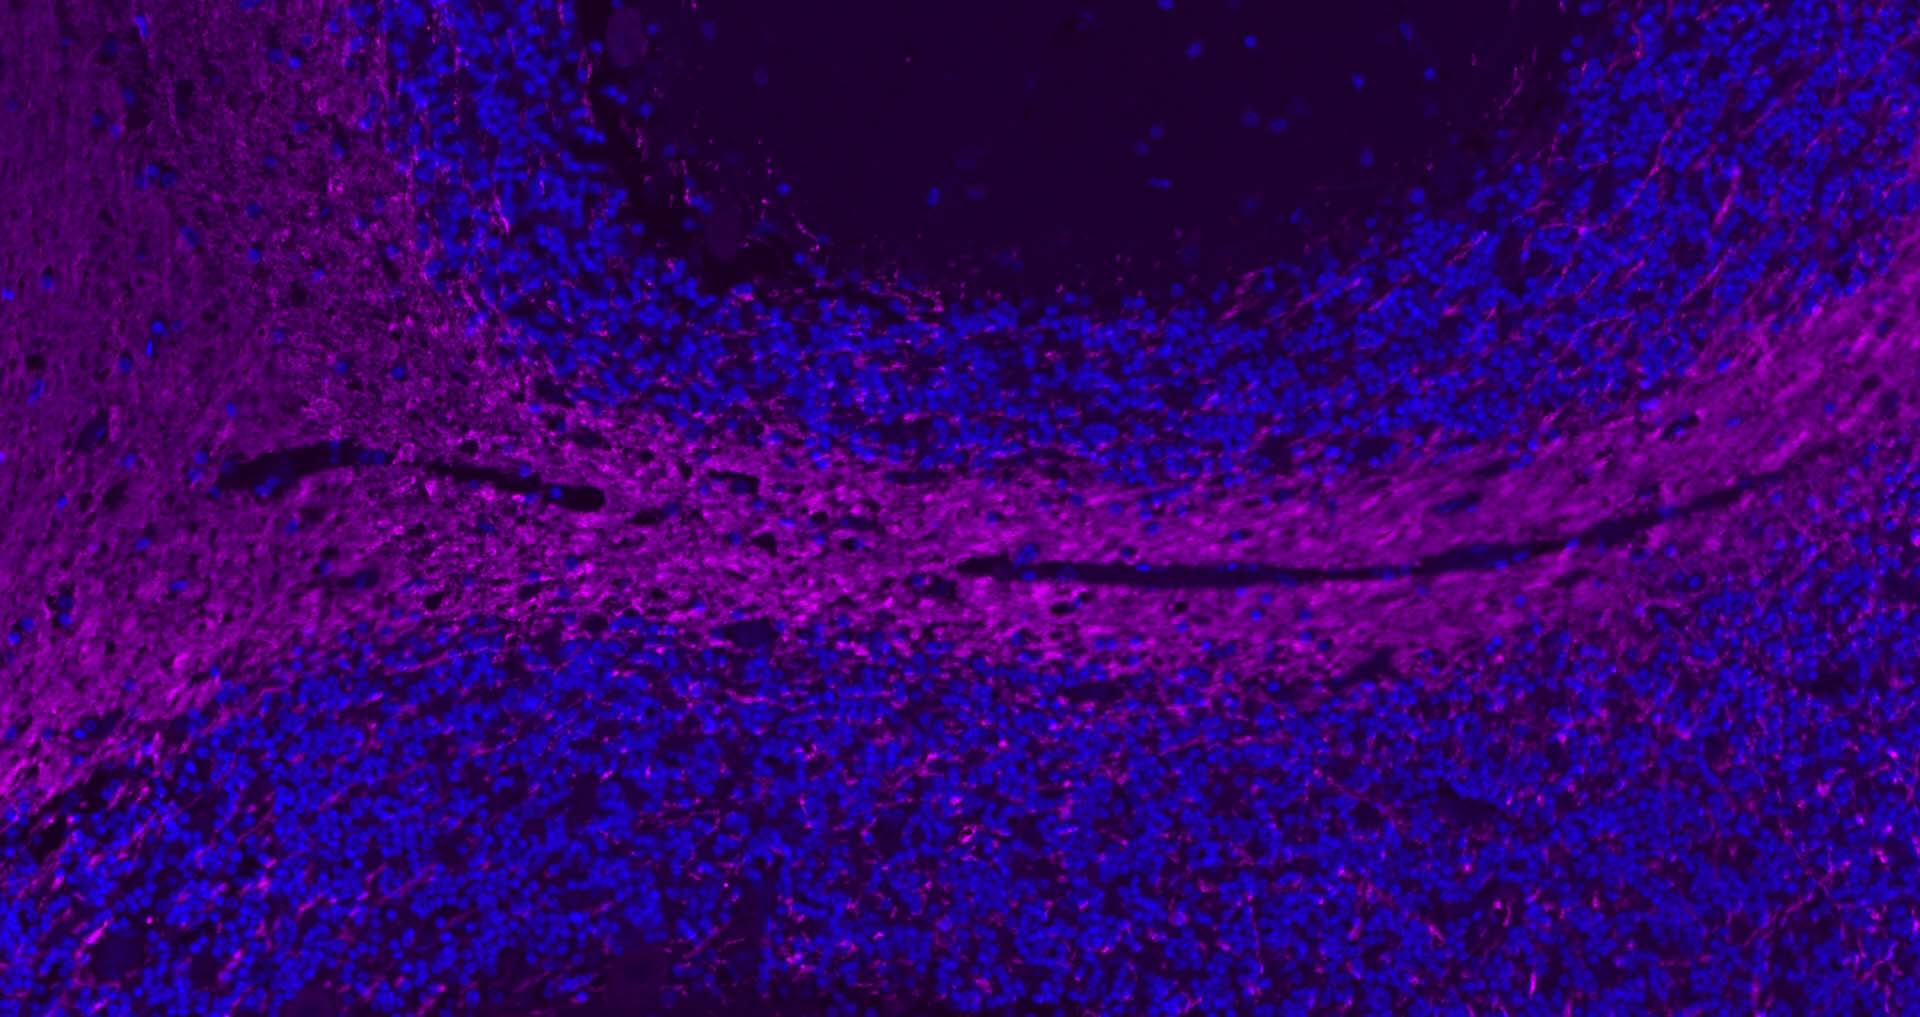

The protein encoded by the classic MBP gene is a major constituent of the myelin sheath of oligodendrocytes and Schwann cells in the nervous system. However, MBP-related transcripts are also present in the bone marrow and the immune system. These mRNAs arise from the long MBP gene (otherwise called "Golli-MBP") that contains 3 additional exons located upstream of the classic MBP exons. Alternative splicing from the Golli and the MBP transcription start sites gives rise to 2 sets of MBP-related transcripts and gene products. The Golli mRNAs contain 3 exons unique to Golli-MBP, spliced in-frame to 1 or more MBP exons. They encode hybrid proteins that have N-terminal Golli aa sequence linked to MBP aa sequence. The second family of transcripts contain only MBP exons and produce the well characterized myelin basic proteins. This complex gene structure is conserved among species suggesting that the MBP transcription unit is an integral part of the Golli transcription unit and that this arrangement is important for the function and/or regulation of these genes.

| IF | Human, Mouse, Rat | Rabbit, Pig, Sheep, Cow, Dog, Horse | 1:500-2000 |